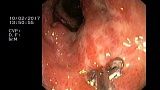

2 мл ( это мин сум, а мы делаем до 10 мл 3% перекись+200 мл физ раствора